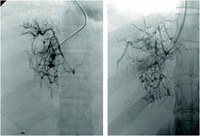

Síndrome de Budd-Chiari: venografia hepática mostrando "teia de aranha" e trombo na veia cava inferior

Liver Transplantation Journal. 2006 Nov;12 (11 supl 2): S21-2; reimpresso com permissão de John Wiley & Sons, Inc